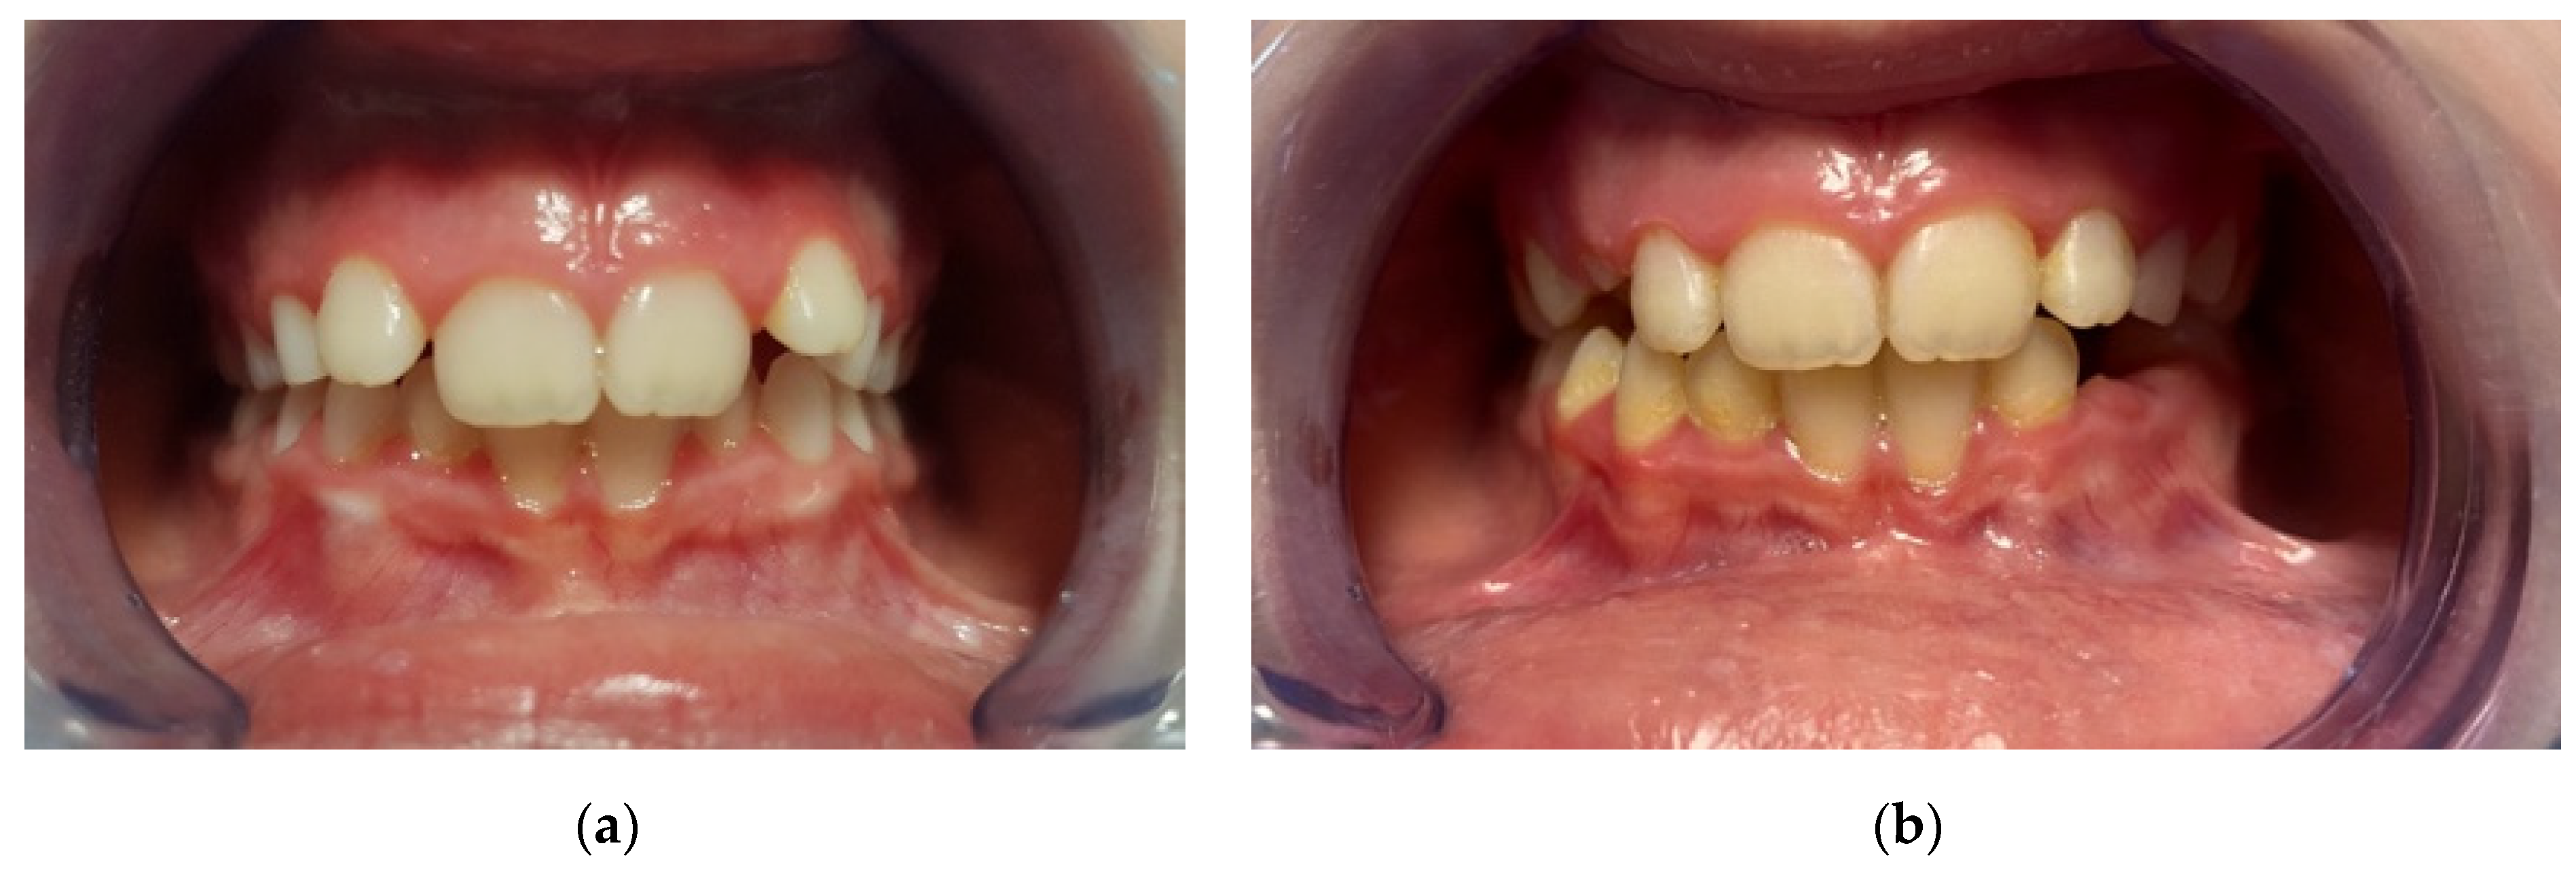

Angle malocclusion (distribution): class I, class II, class I/II.

Figure 2. Comparative evaluation of cephalometric analysis performed at T0 (a) and T1 (b) to identify potential skeletal and dentoalveolar changes in sagittal and vertical relation.